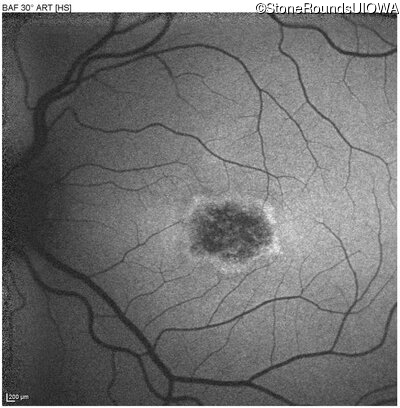

Blue Autofluorescence - Right - 20/100 -2 sc

Exemplar